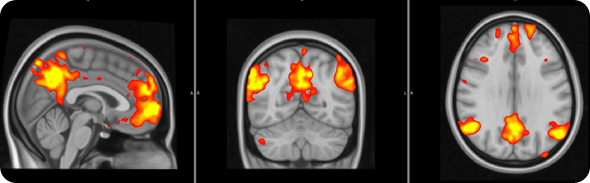

In order to address this question, we used a brain imaging technique called ‘functional Magnetic Resonance Imaging’, which allows us to examine how brain activity changes in association with certain states or tasks.

In this study brain activity was investigated when the participants received painful stimuli, as well as when they received visual cues informing the subjects of impending pain onset (pain anticipation) and pain offset (relief anticipation).

We saw that the healthy subjects showed large brain responses, in many regions, when they were anticipating pain or relief. Some of these changes are likely to be due to the detection of ‘salient’ event. In other words, some of these responses may be non pain-specific and may simply reflect the fact that the subjects were detecting an ‘interesting event’.

FM patients exhibited reduced brain responses in response to visual cues for both pain anticipation as well as relief anticipation.

This reduced responsiveness was very widespread, and included the periaqueductal gray and the VTA.